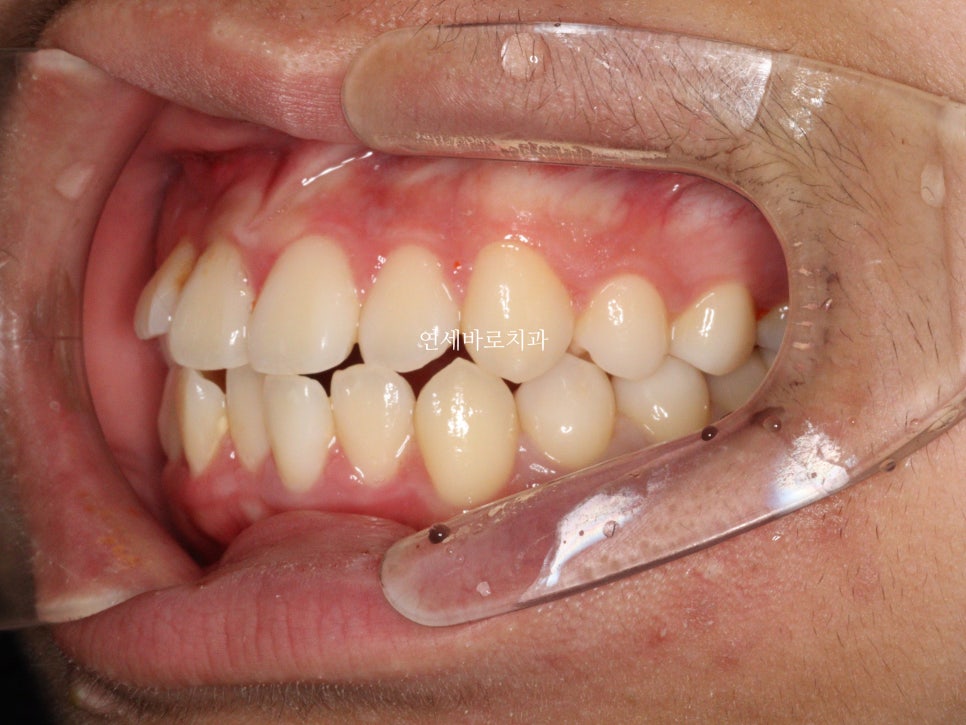

이렇게 보니 차이가 조금 더 크죠?

이런 문제가 있지만 송곳니 발치는 종종 선택되어 집니다.